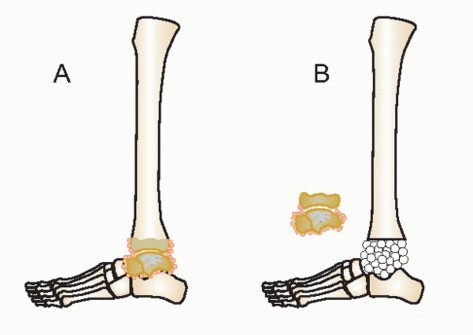

Excision of the talus causes 3 to 4 cm of leg length discrepancy (FIG 2). This defect can be reconstructed with internal fixation and bone grafting to maintain leg length.16

FIG 2 • CT scan of tibiocalcaneal arthrodesis. The excision of the talus creates a 3- to 4-cm bone defect.*